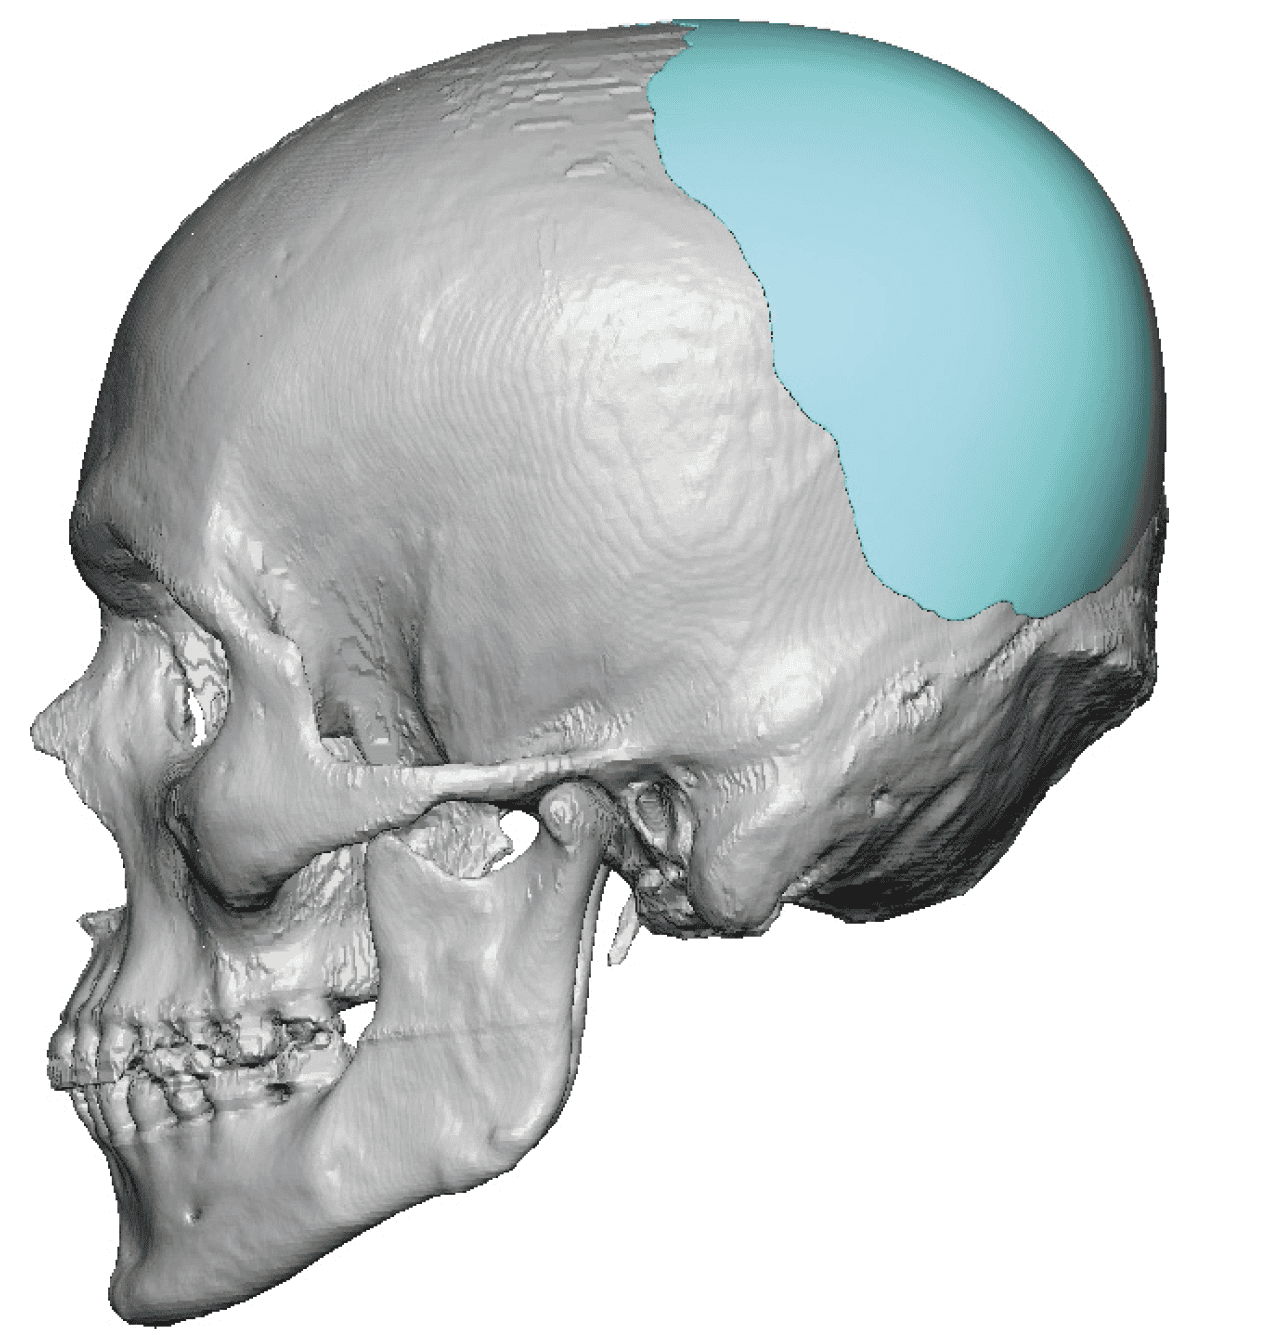

Patient 100

Desire for reshaping of an asymmetric flat back of the head in a shaved head male.

A combined back of the head reshaping procedure was done with a custom skull implant, sagittal ridge reduction and a right temporal muscle reduction.

Desire for reshaping of an asymmetric flat back of the head in a shaved head male.

A combined back of the head reshaping procedure was done with a custom skull implant, sagittal ridge reduction and a right temporal muscle reduction.